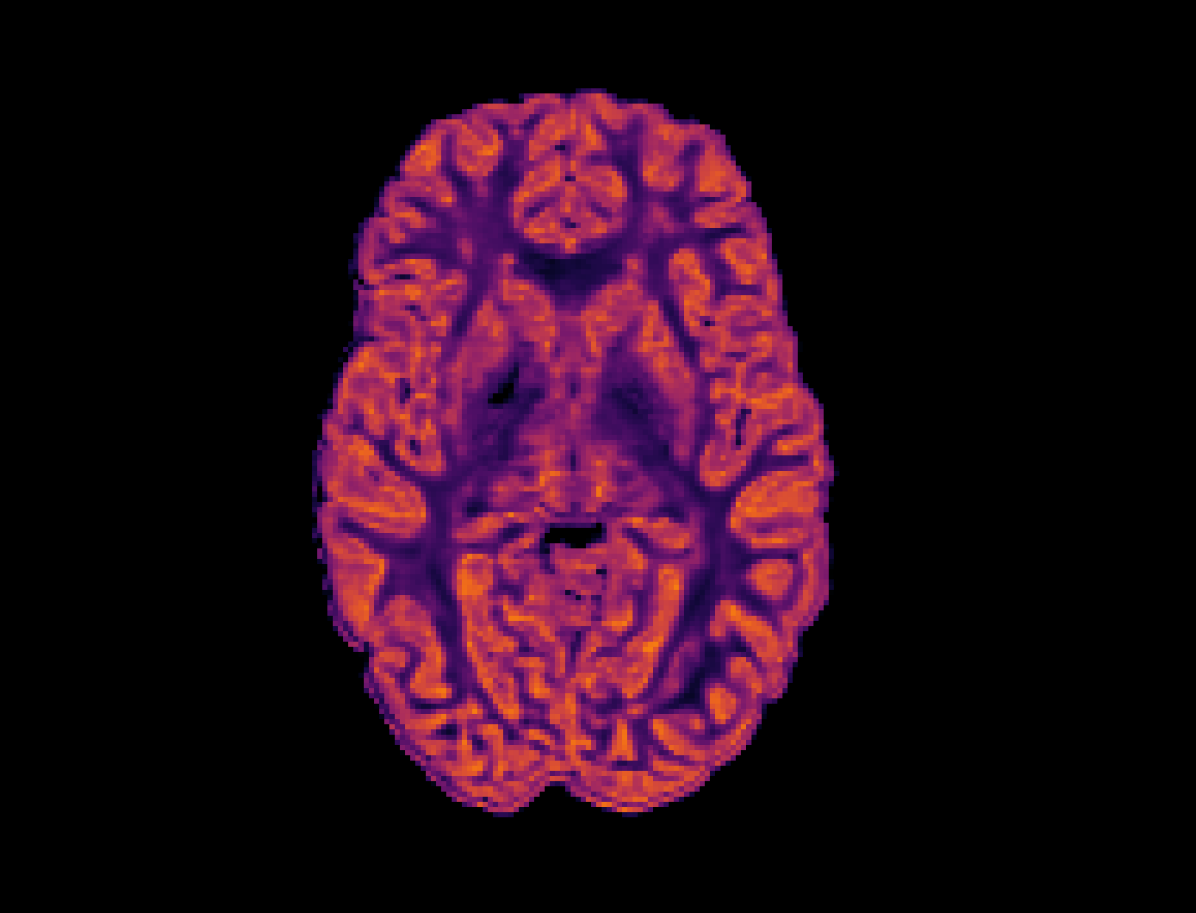

Refer to caption

(a) High Resolution

(b) SR-q-DL

(c) RCNN

Refer to captionRefer to caption

(d) PCCNN-Bv

Figure 4: Axial slice of orientation dispersion index (OD) within one subject across different models. Models use single-shell data (b=1000s/mm2𝑏1000ssuperscriptmm2b=1000\mathrm{s/mm^{2}}) with angular dimension size qin=10subscript𝑞in10q_{\mathrm{in}}=10 as input, and produce 808080 b=1000s/mm2𝑏1000ssuperscriptmm2b=1000\mathrm{s/mm^{2}}, 909090 b=2000s/mm2𝑏2000ssuperscriptmm2b=2000\mathrm{s/mm^{2}}, and 909090 b=3000s/mm2𝑏3000ssuperscriptmm2b=3000\mathrm{s/mm^{2}} inferred volumes.

In this experiment, the PCCNN models perform competitively, yielding the lowest error in fisosubscript𝑓isof_{\mathrm{iso}} and fintrasubscript𝑓intraf_{\mathrm{intra}} across all three sub-sampling rates. The relative error in OD across different models mirrors that of the FOD ACC found in Table 4, suggesting that the trained models are able to infer data that generalise across different downstream analyses. The worst performing model across all sub-sampling schemes was the SR-q-DL model, as is demonstrated qualitatively by Figure 4. Whilst this model could benefit from the more constrained task of inferring NODDI data directly, the lack of geometric prior information, such as b-vector coordinates, suggests that these additions within the PCCNN models were important to its relatively high performance in this task.